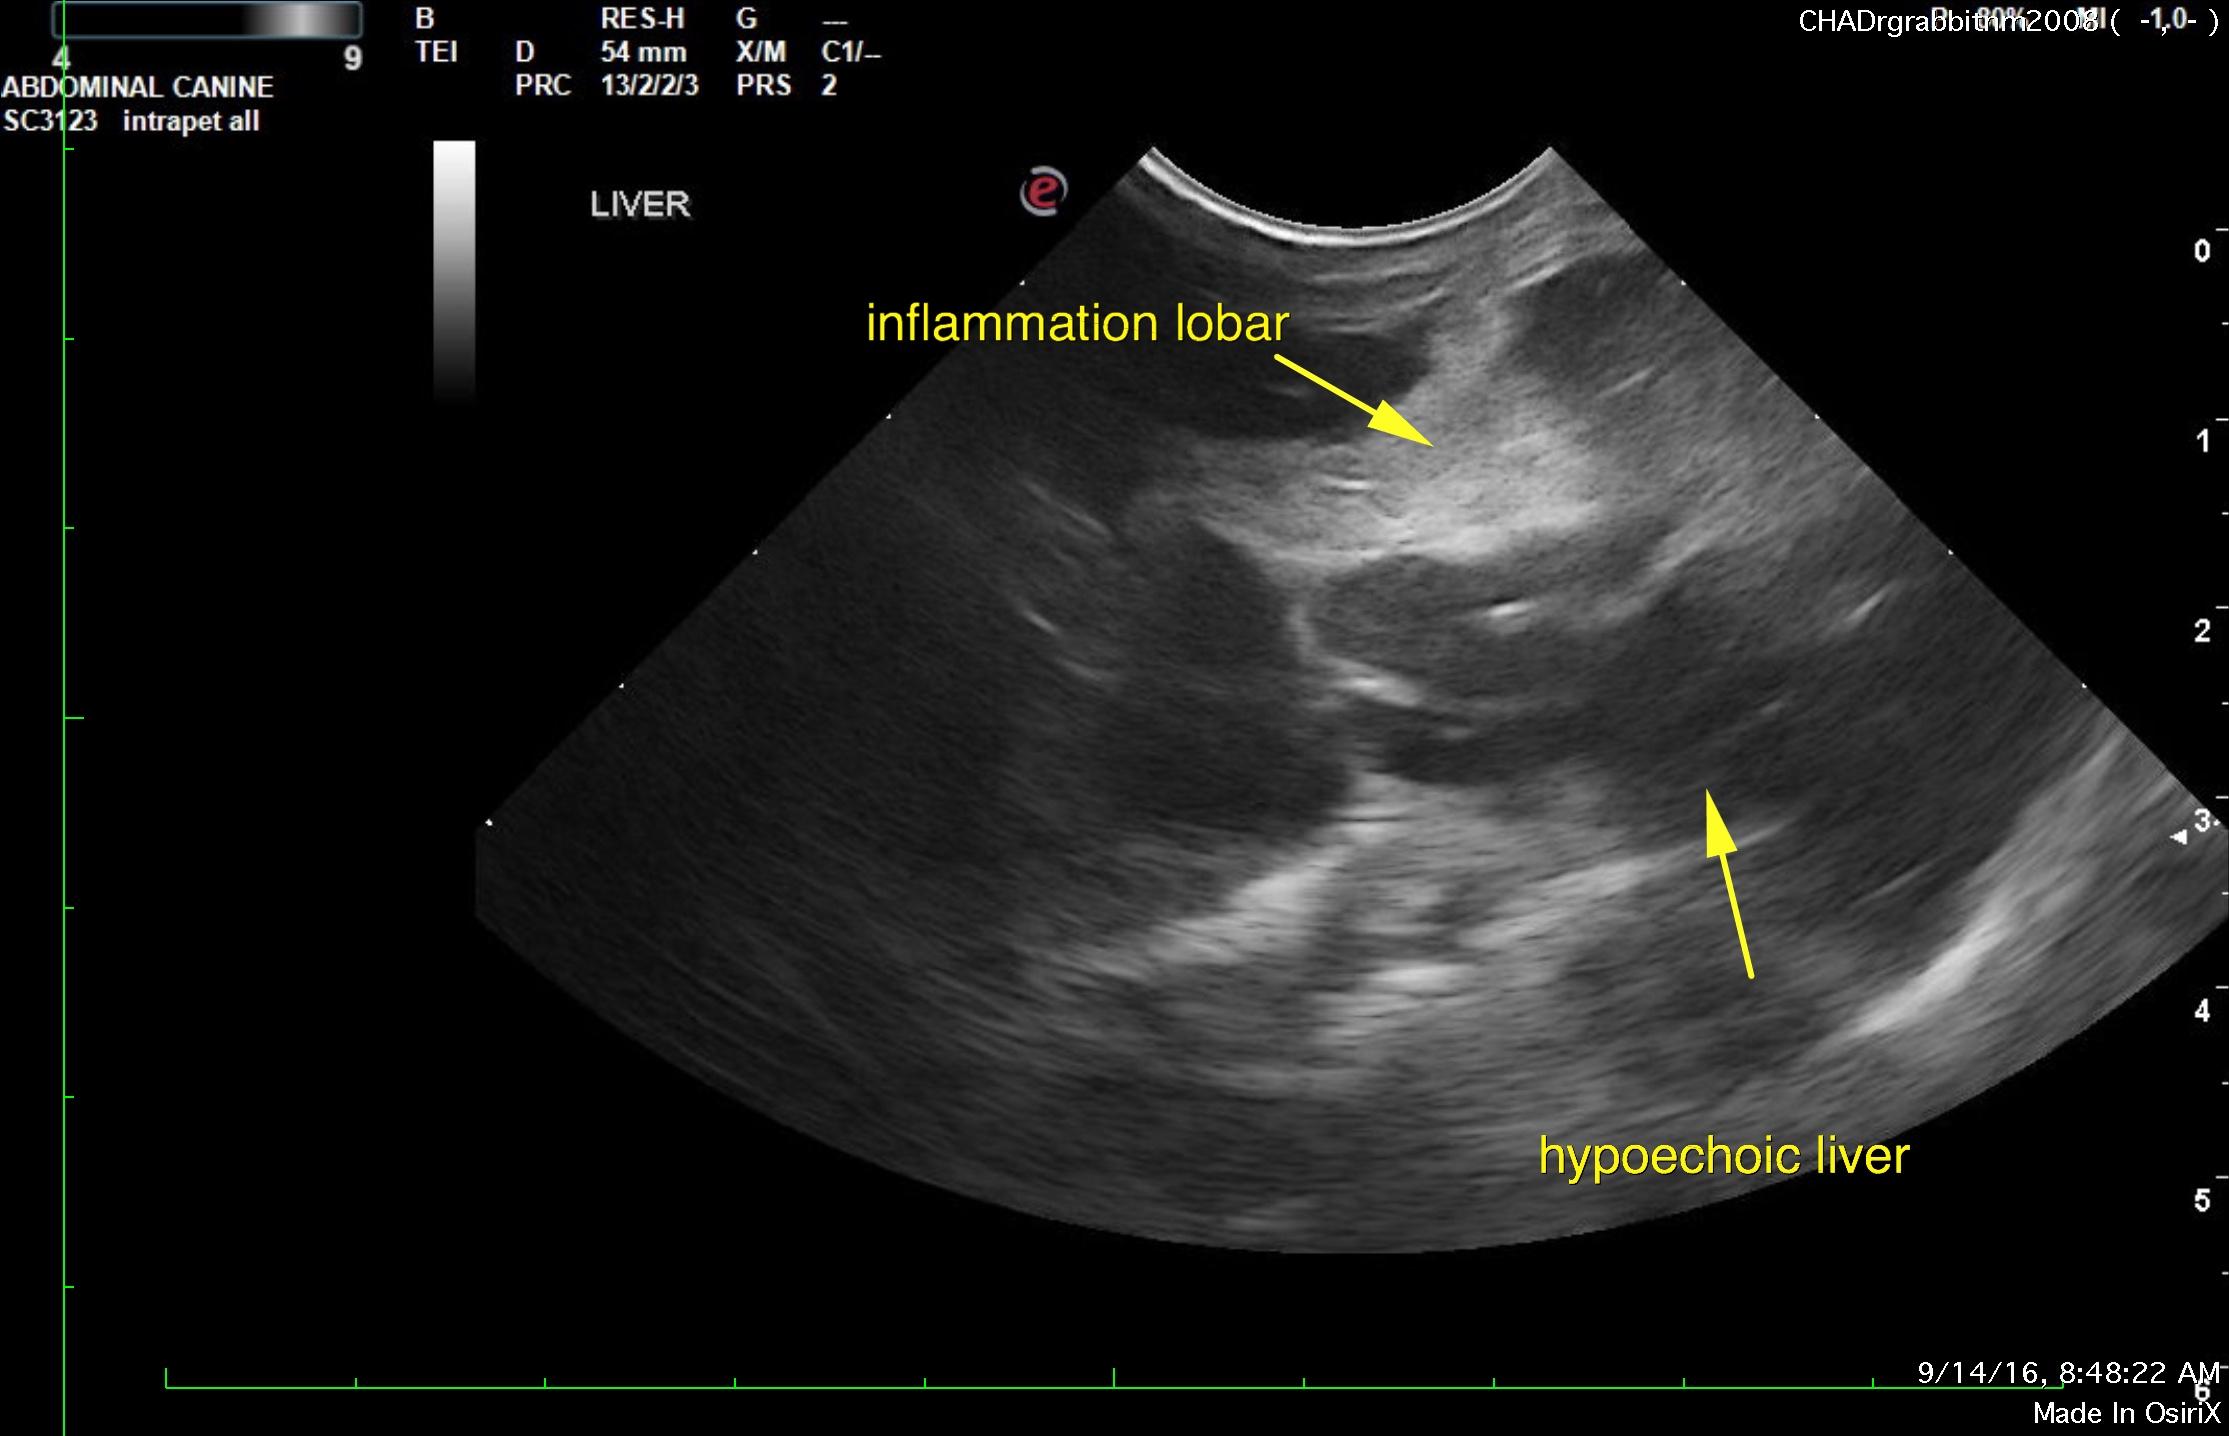

From members.sonopath.com

Liver lobe torsion in a 8 year old MN rabbit Members Rabbit Liver Lobes Find out how to diagnose and treat liver disease in rabbits with bloodwork, ultrasound, and other tests. The prevalence of liver lobe torsion was 0.7% (82/11,402). The rabbit liver consists of five lobes: Practitioners should recommend initial diagnostics including. Fifty (60.1%) rabbits underwent liver lobectomy, 23 (28%) received medical treatment alone, and 9 (10.9%) were euthanized or died on presentation.. Rabbit Liver Lobes.

Image Liver torsion, rabbit MSD Veterinary Manual Rabbit Liver Lobes Find out how to diagnose and treat liver disease in rabbits with bloodwork, ultrasound, and other tests. Practitioners should recommend initial diagnostics including. The prevalence of liver lobe torsion was 0.7% (82/11,402). This article reviews diagnosis and management of liver lobe torsion in rabbits. Fifty (60.1%) rabbits underwent liver lobectomy, 23 (28%) received medical treatment alone, and 9 (10.9%) were. Rabbit Liver Lobes.